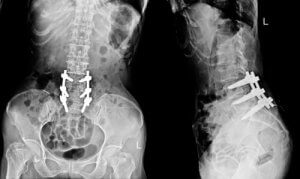

- Спондилодез. Это наиболее распространенная операция, выполняемая при хронической неспецифической боли в спине, связанной с дегенеративными изменениям. Целью операции является соединение (слияние) двух позвонков для стабилизации позвоночника. Это ограничивает подвижность пораженной области позвоночника, но не сильно отражается на двигательной активности пациента. В настоящее время спондилодез может проводиться минимально инвазивным путем.

- Фиксация позвоночника